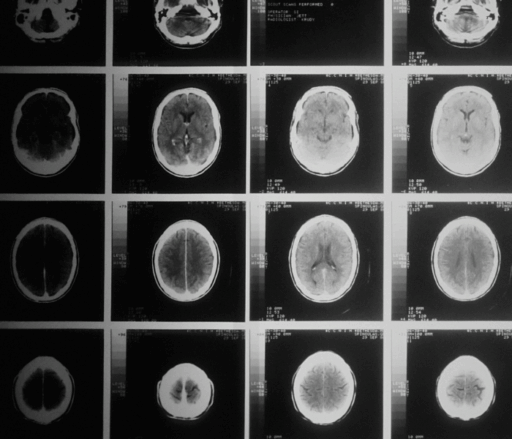

With dementia rates forecast to reach 78 million people globally by 2030, tackling dementia requires a truly international and local effort. We support and work with Alzheimer and dementia associations in over 100 countries, as well as people living with dementia, carers and all relevant organisations to help raise awareness, challenge stigma and to call for dementia to be a global health priority.

The 2025 World Alzheimer Report explores the important topic of dementia rehabilitation, examining how the concept is defined and implemented, as well as practical considerations of how to best adapt rehabilitation practices for people living with dementia in different contexts.